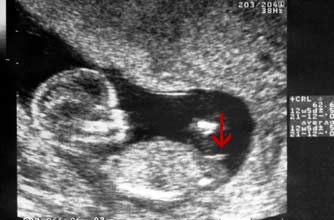

nt检查的时候,医生一般是能看到二维超声的全景图的,也就是宝宝的全身,报告上也有可能会放全身图,NT单子上会有宝宝的图片,可以根据英国的nub点原理来判断男女,nub theory指的是通过NT检查图片上的胎儿特征点和尾椎的角度判断男女的方法,男孩的特征点与身体呈30度角,还多一些,而女孩儿的特征点几乎和躯体平行。还有就是如果是男宝宝,屁股位置会微微上翘,后背脊柱成圆弧状,因为要留空间发育前列腺,相反,女宝宝后背脊柱就相对就平一些。